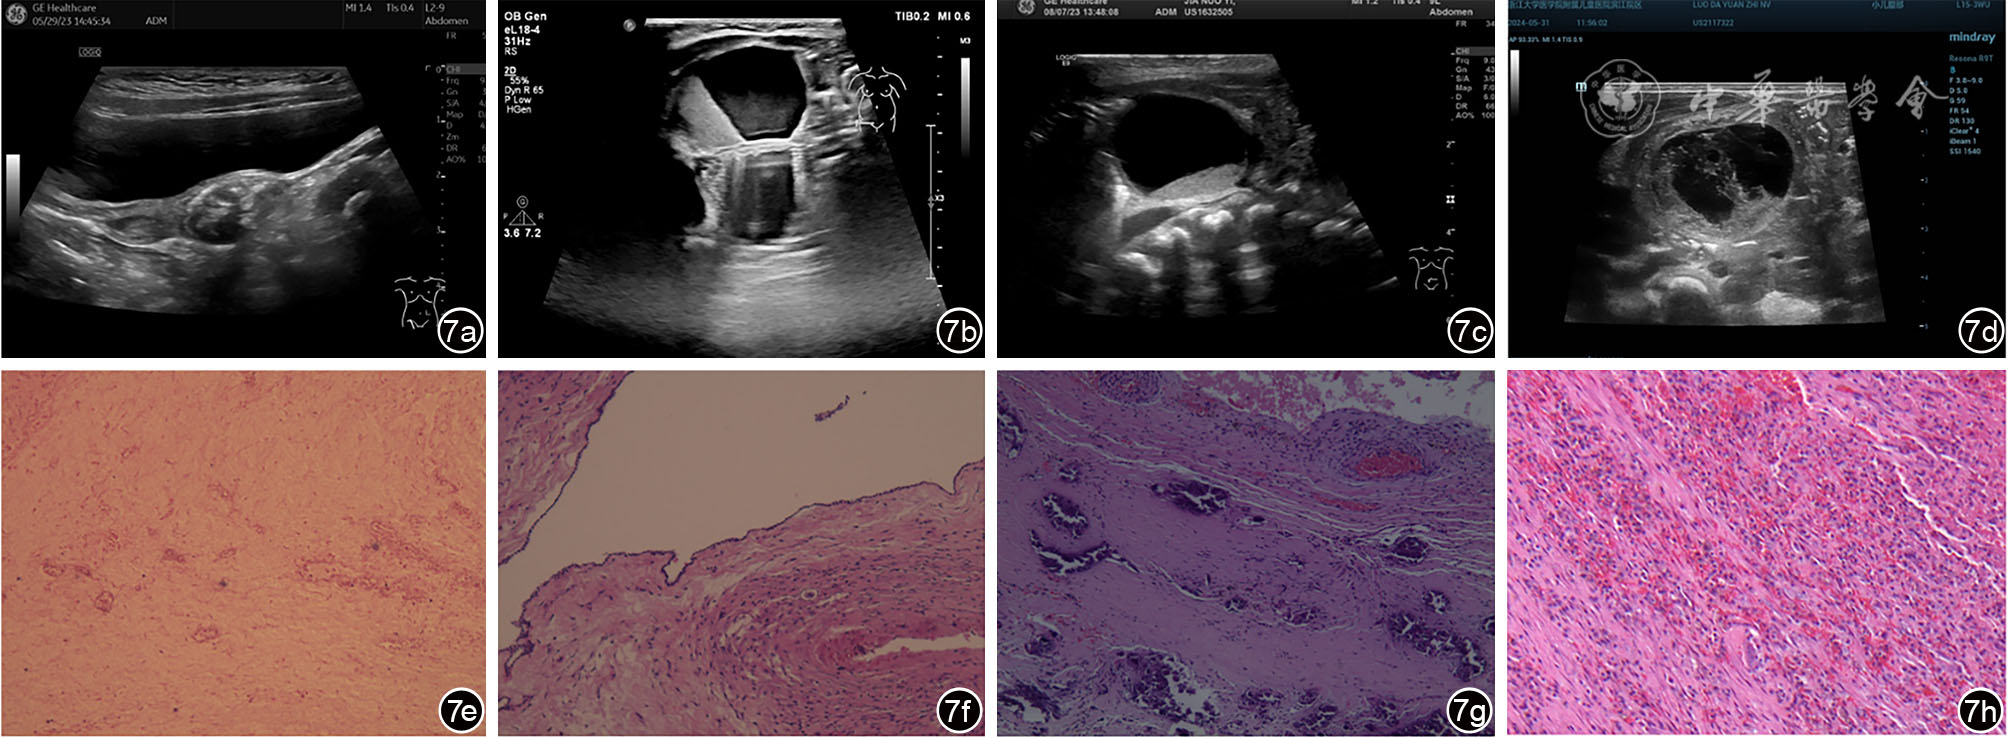

图7 陈旧性卵巢囊肿蒂扭转超声误诊病例超声及病理表现。图a为女性婴幼儿,出生12个月,超声可见盆腔内不均质团块回声,内见斑片状强回声伴声影,超声诊断左侧卵巢来源畸胎瘤;图b为女性婴幼儿,出生1个月,超声可见右侧附件区囊性包块,内见液体分层征,超声诊断右附件畸胎瘤;图c为女性新生儿,出生4 d,超声可见盆腔内囊实性包块,内见液体分层征,超声诊断盆腔囊实性包块,畸胎瘤待排;图d为女性新生儿,出生3 d,超声可见右侧腹囊性包块,内透声差,见分隔,超声诊断右侧腹囊性包块,肠重复畸形可能;图e(与图a为同一病例)病理提示左侧卵巢组织广泛坏死伴钙化改变,可见少许深蓝色团块状沉积和细胞核的碎裂消失(HE ×40);图f(与图b为同一病例)病理提示卵巢单纯性囊肿伴坏死钙化,可见散在细胞核的碎裂消失(HE ×100);图g(与图c为同一病例)病理提示卵巢囊肿蒂扭转伴坏死,可见深蓝色团块状沉积和红细胞在血管外聚集(HE ×200);图h(与图d为同一病例)病理提示卵巢囊肿蒂扭转伴出血坏死钙化,可见红细胞散在分布(HE ×200)